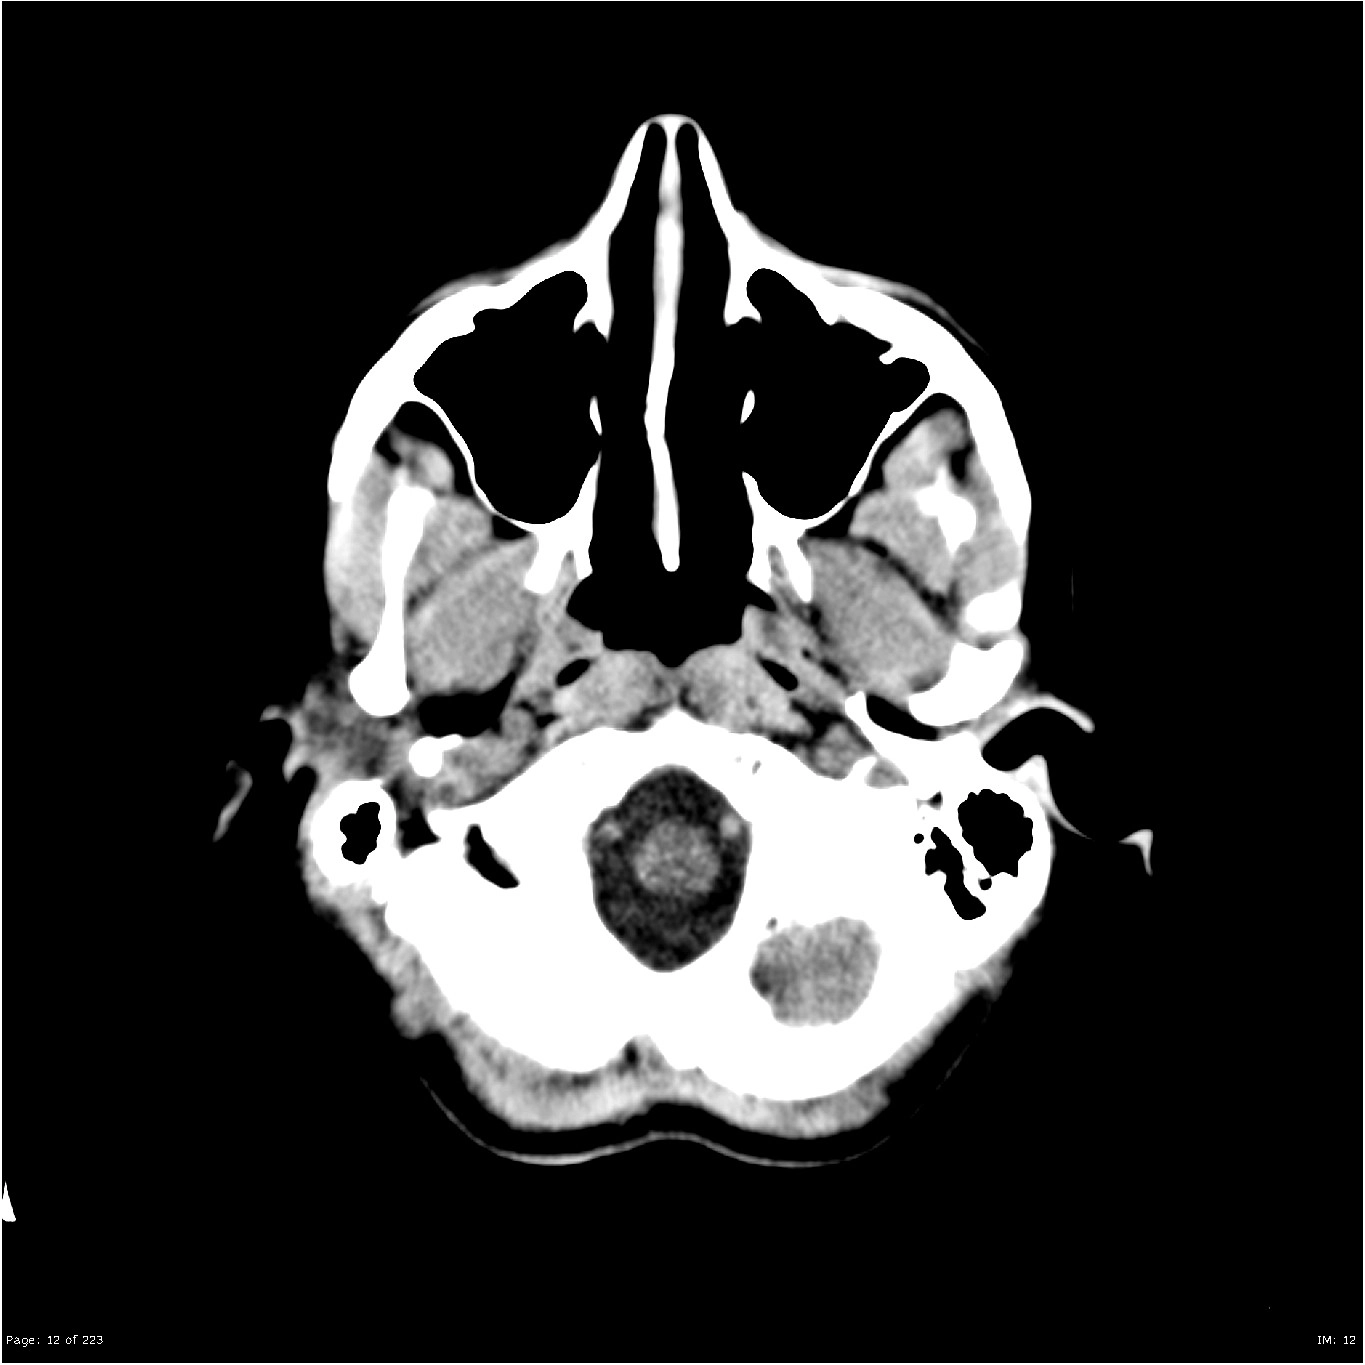

Nang thượng bì góc cầu tiểu não (CPA-IAC Epidermoid Cyst)